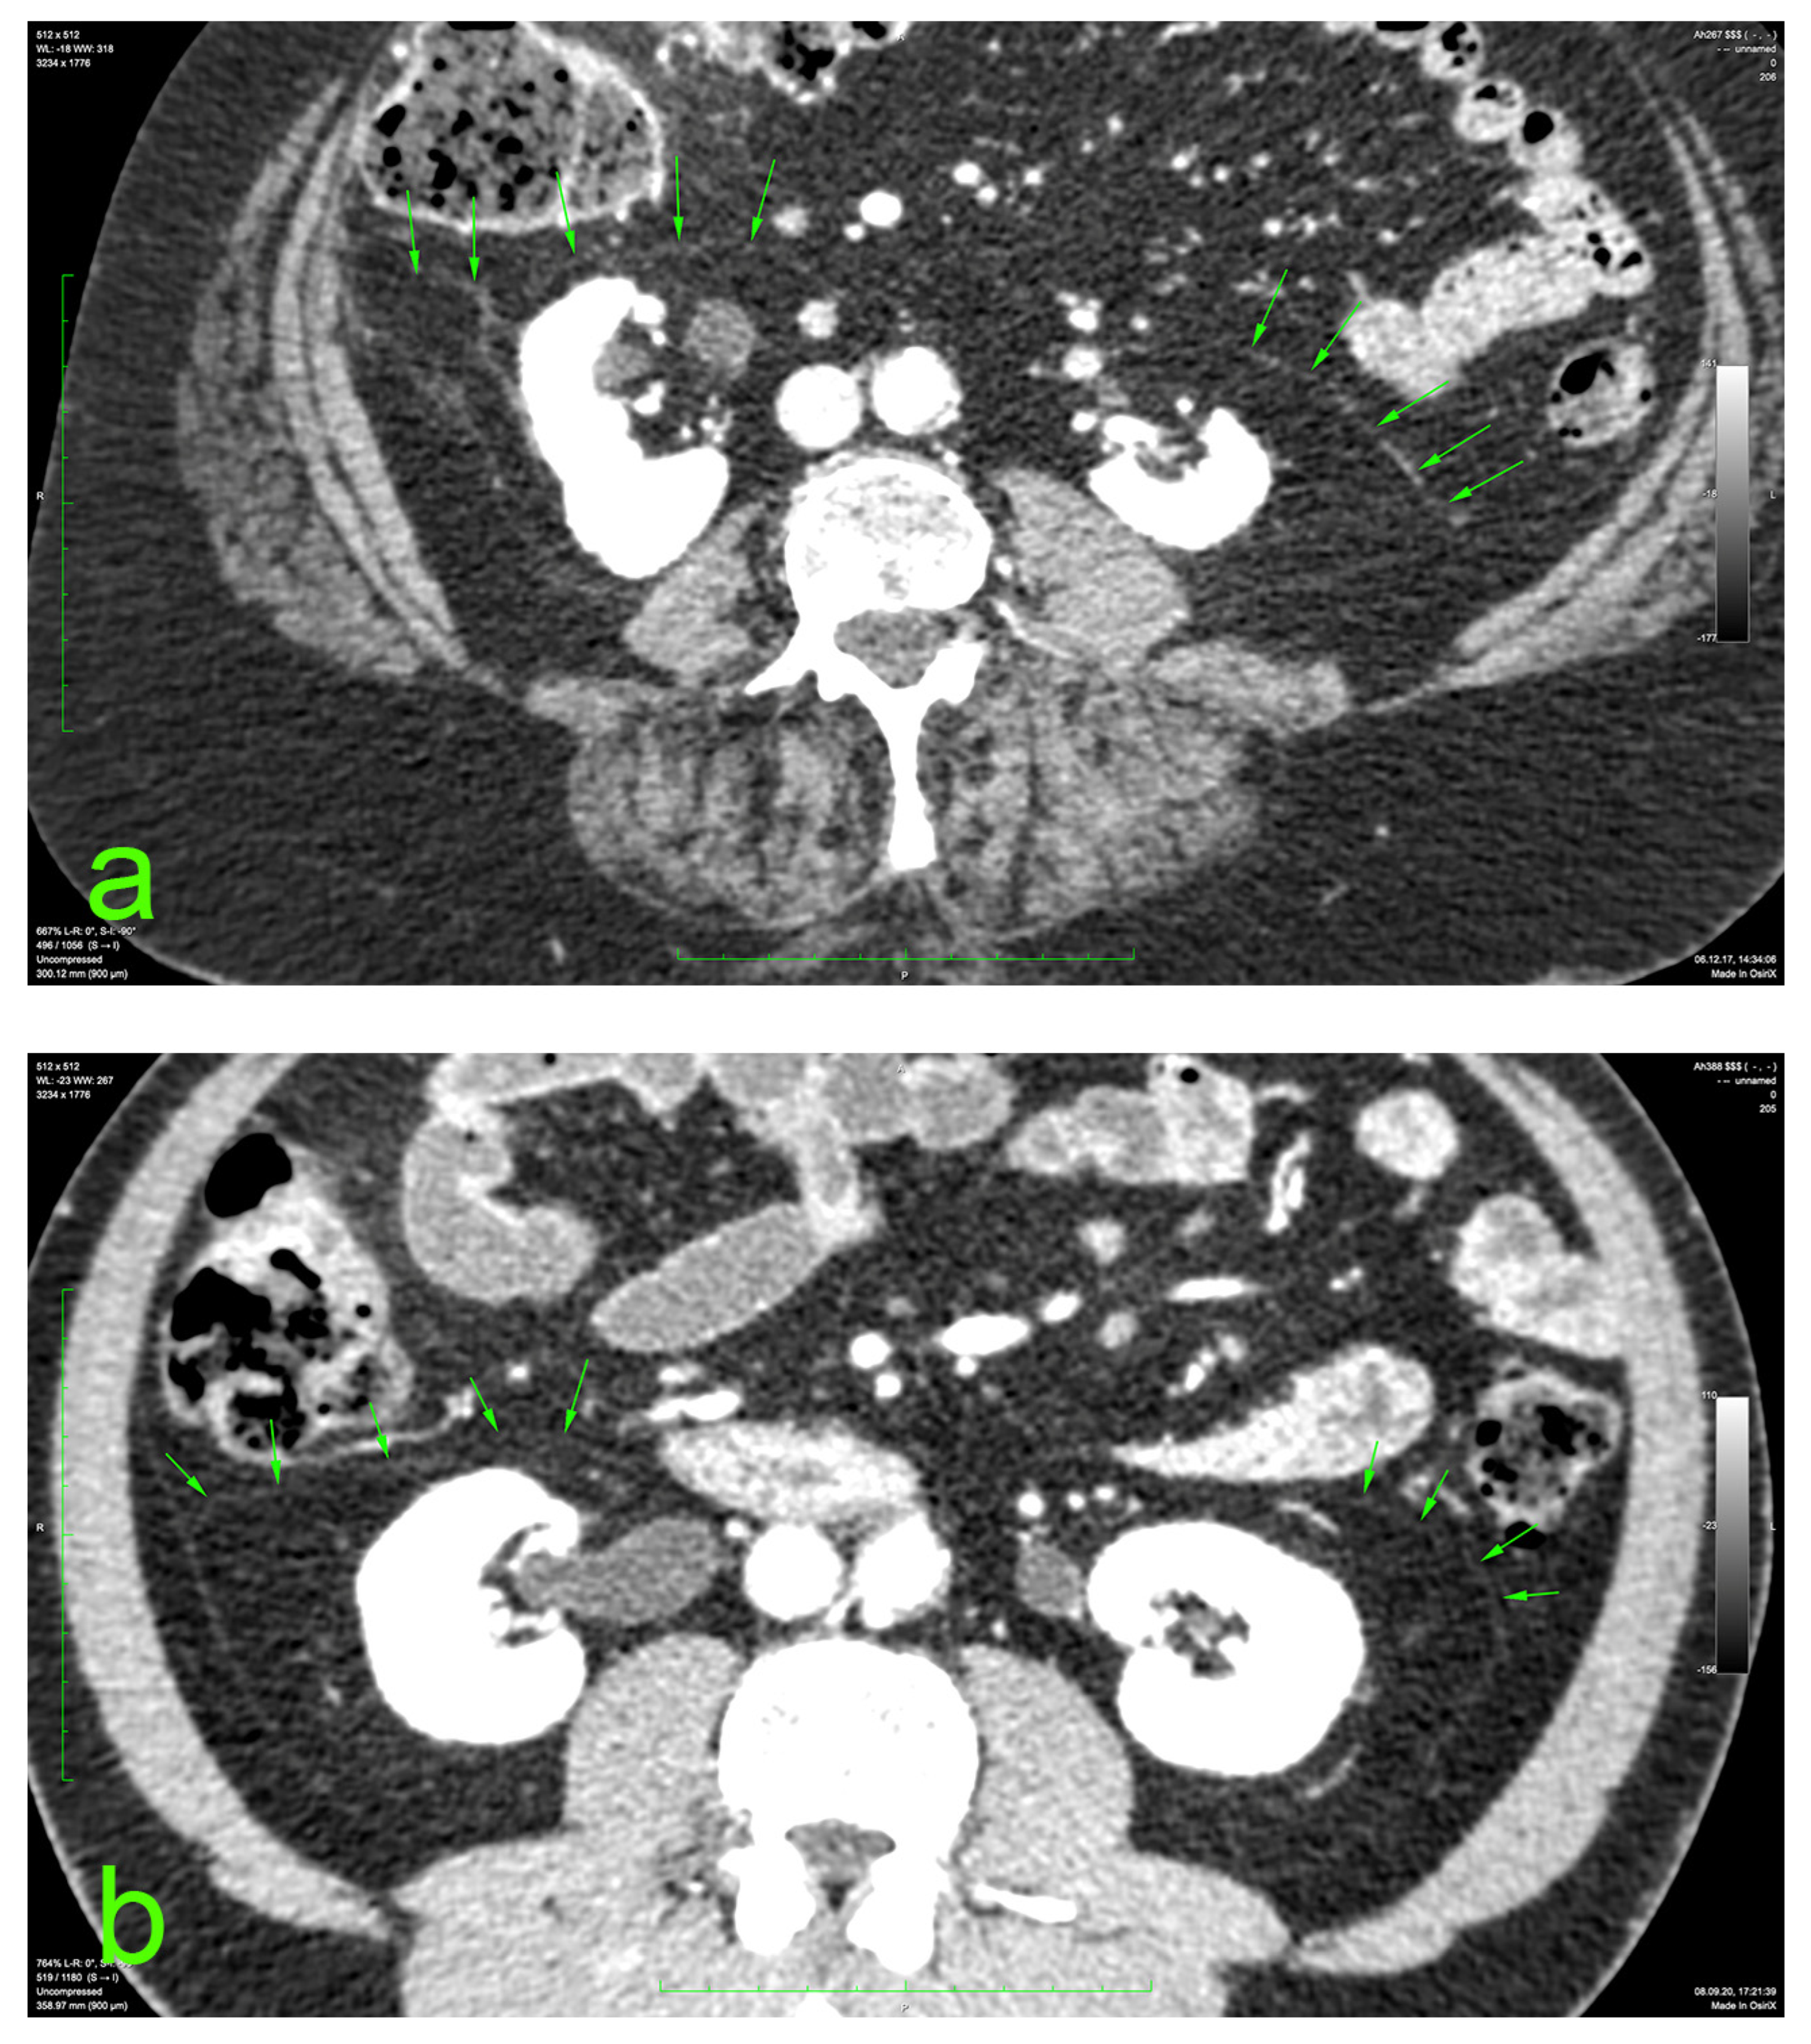

The principal portion of this study was also based on the aforementioned CT datasets. They were analyzed using a 2D multiplanar reconstruction with a maximum intensity projection with the aid of Food and Drug Administration (FDA)—approved Osirix MD v.14.0 64-bit image-processing application software (Pixmeo, Bernex, Switzerland). The wide area behind the ascending and descending colon was analyzed for the appearance of the distinct retrocolic fascia. The thickness of this fascia was measured at four arbitrary levels, related to the kidneys, on both sides (left and right): upper pole, midlevel, lower pole, and below the lower kidney pole. Each measurement was performed twice, calculating the arithmetic mean for each level. The final thickness (tool Length) of one side was defined as the mean value of the four measurements (Figure 1).

Figure 1.

Prerenal fasciae (green arrows) on injected CT: (a) 70-year-old female patient with a BMI of 32.9; (b) 50-year-old male patient with a BMI of 30.1.